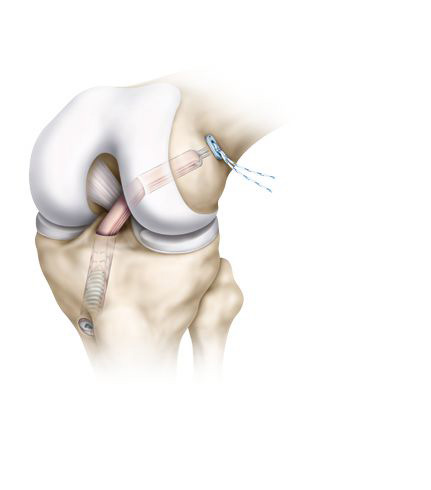

Indicadas para fornecer meios de fixação do osso e ajudá-lo na gerência das fraturas e de cirurgias de reconstrução do ligamento Cruzado Anterior (LCA) e ligamento Cruzado Posterior (LCP), fornecendo fixação no reparo de tendões e ligamentos.

No tratamento das instabilidades anteriores e posteriores do joelho. Permitindo assim a reconstrução endoscópica para enxertia dos ligamentos citados com os tendões dos músculos: patelar, tendão flexor, semitendinoso e grácil.

Sistema de Reconstrução se caracteriza como um dispositivo de reconstrução ligamentar de tamanho único. Sua principal aplicação ocorre em lesões do ligamento cruzado (LCA / LCP).

- O Sistema é compatível com todos os instrumentais disponíveis no mercado, que estão relacionados à técnica de reconstrução ligamentar.